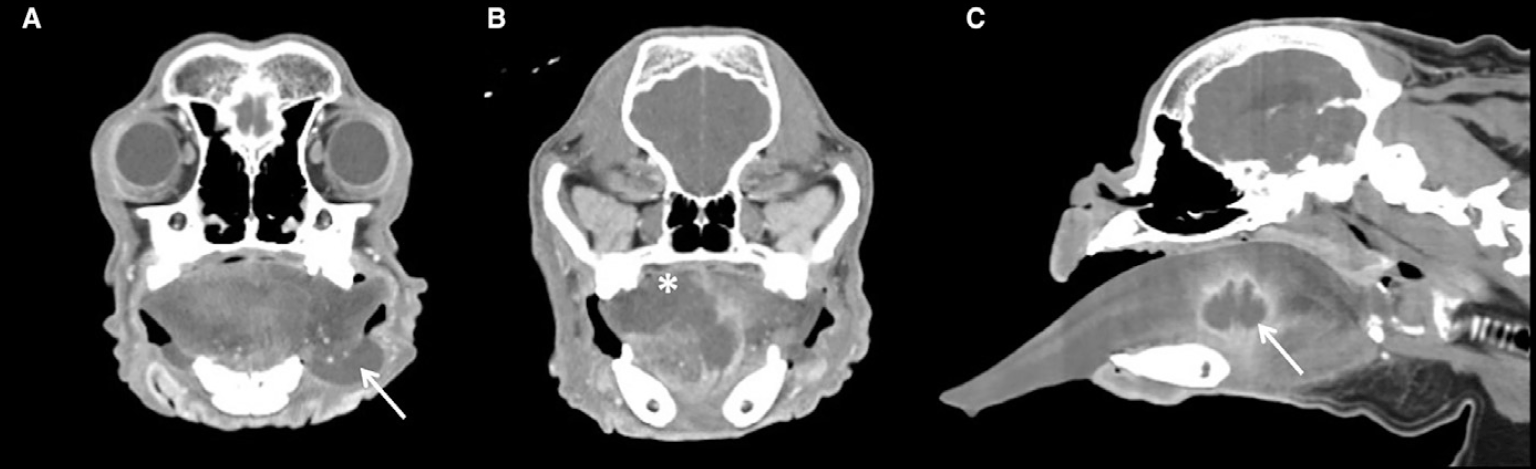

첫째, CT 검사를 통해 병변의 형태와 범위를 확인했습니다.

급성으로 발생한 혀 부종과 종괴 소견을 바탕으로 알레르기 반응, 외상, 이물, 종양성 변화 등이 감별진단으로 고려되었고 이에 따라 CT 검사가 진행되었습니다.CT 결과 혀는 현저히 커져 있었으며 혀의 뿌리에서 몸통까지 이어지는 공동성 병변이 확인되었습니다.

또한 조영 후 영상에서는 rim enhancement가 관찰되어 설농양을 시사하는 소견으로 판단되었습니다.

저자들은 이러한 상황에서 영상검사가 도움이 될 수 있다고 언급하고 있으며 특히 이번 증례에서는 CT를 통해 병변의 위치와 특성을 확인하는 데 유용한 정보를 얻을 수 있었다고 정리하고 있습니다.

또한 저자들은 “To our knowledge, this is the first report of CT findings of a lingual abscess in a dog”라고 기술하고 있어 이번 논문이 개에서 발생한 설농양의 CT 소견을 보고한 첫 증례라는 점을 강조하고 있습니다.